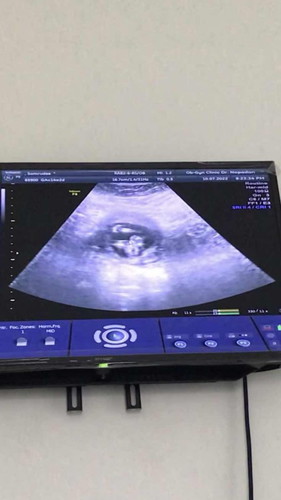

ภาพอัลตร้าซาวด์

แบบนี้ ผช.หรือ ผญ.คะ พึ่ง14wเองค่ะ ลองถามคุนหมอ คุนหมอเดาให้ว่าตอนนี้เป็น ผญ. มีโอกาศจะเป็น ผช.หรือเปล่าคะ